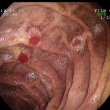

Schönlein-Henoch purpura a leszálló duodenumban, mellette kis ectopiás pancreas metaplasia

1. kép: Schönlein-Henoch purpura a leszálló duodenumban, mellette kis ectopiás pancreas metaplasia